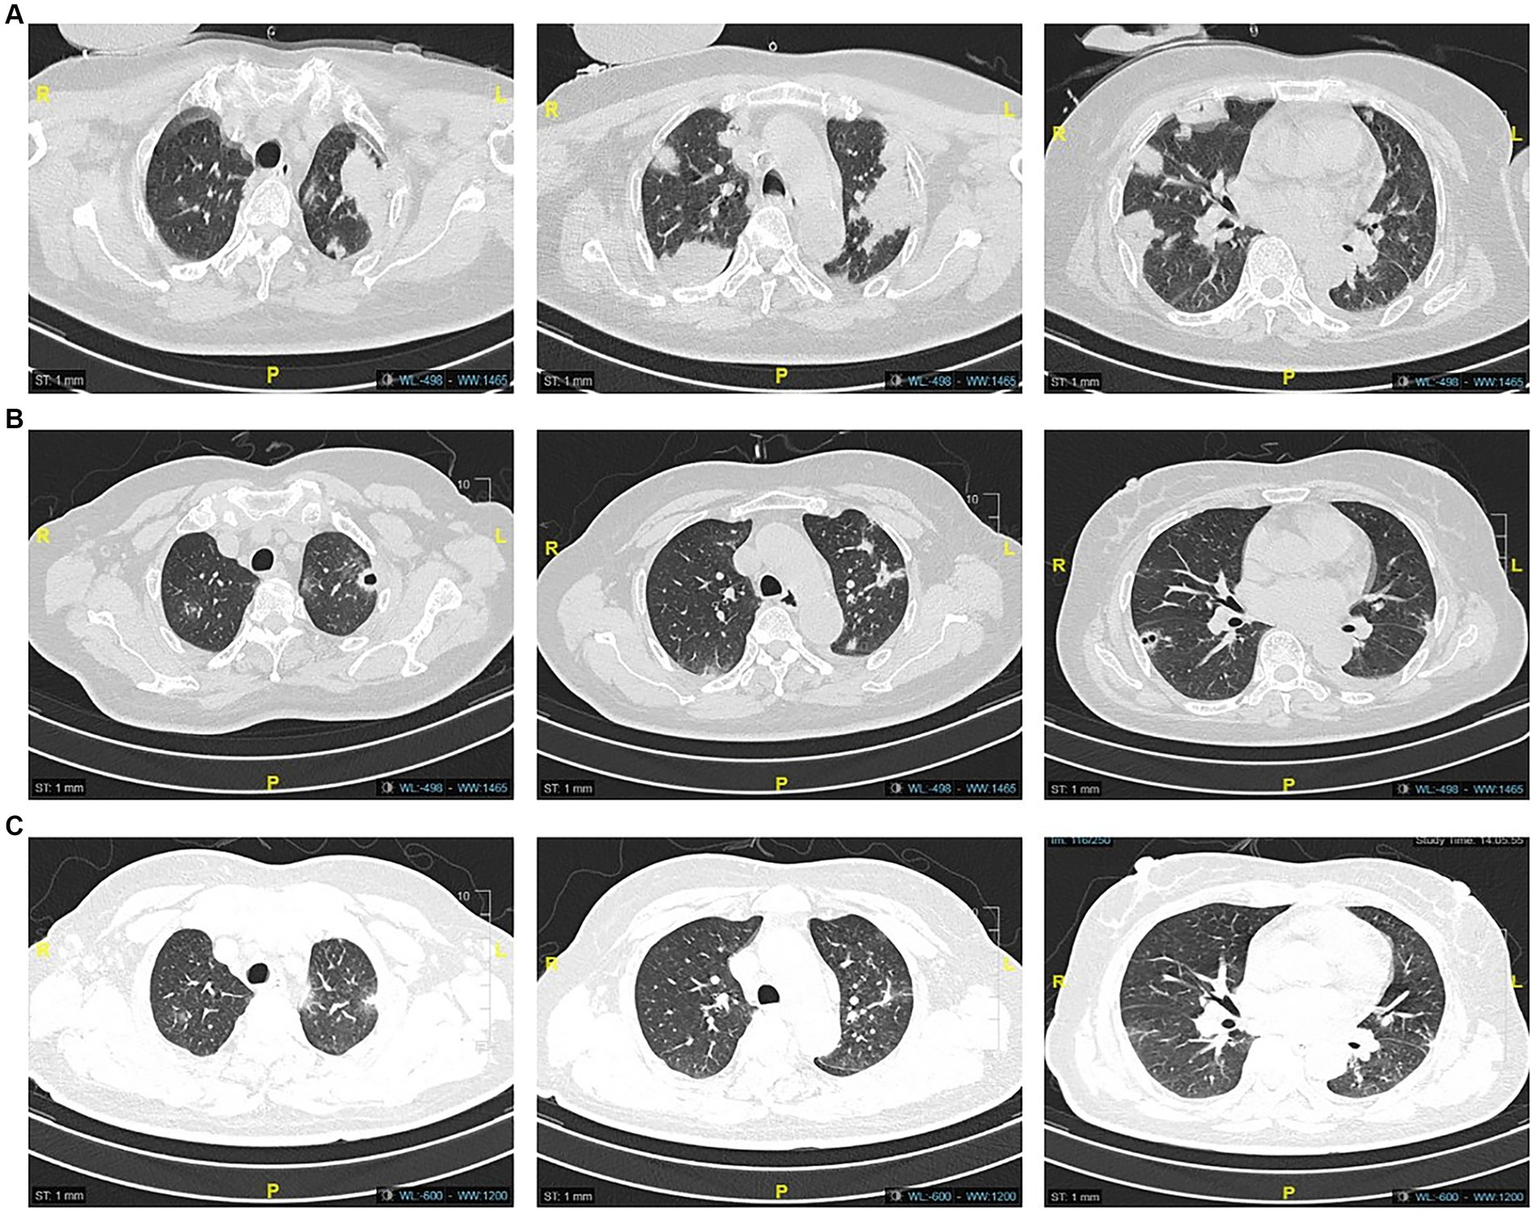

A 60-year-old female was admitted to the hospital on August 1, 2022, due to 1 week of recurrent fever with progressive dyspnea, with a previous history of type 2 diabetes. Her chest CT showed multiple masses and cavity changes in both lungs (Figure 1A), and the blood culture showed bilateral aerobic bottle growth of Klebsiella pneumonia. A diagnosis of a hematogenous pulmonary abscess was made. The drug sensitivity results of blood culture suggested sensitivity to piperacillin-tazobactam, which was then administered as an anti-infective agent.

Figure 1

Computed tomography images on admission showed multiple mass shadows (A), and CT images after 15 days of piperacillin-tazobactam anti-infection treatment showed partial resorption of the lung lesions in comparison (B). The lesions continued to resorb after 30 days (C).

During the treatment period, the patient’s symptoms gradually improved, and the lesion was partially absorbed on Day 15 upon review of the chest CT (Figure 1B). On Day 26, the patient developed a low fever, with her temperature reaching 37.8°C. Three days later, she began to develop a punctate red rash in the front chest and forearm of both upper limbs with pruritic discomfort (Figure 2). We could not rule out delayed drug allergy after a dermatology consultation, so we discontinued the use of piperacillin-tazobactam. The range of the posterior rash expanded to the face and lower limbs (Figure 2), the occipital and mandibular lymph nodes became enlarged, and the body temperature increased to a maximum of 39.5°C. A repeat chest CT showed continued improvement of the lesion (Figure 1C). Fever-related tests, such as pneumonia pathogen detection, rheumatoid immune complexes, and ferritin, were completed, and all results were negative. The patient had a gradual rise in eosinophils to 1.33*109/L, leukocytes to 18.47*109/L, and lymphocytes to 7.70*109/L, as well as a significant increase in abnormal lymphocytes (7%) accompanied by abnormal liver function, with an ALT level of 114 U/L, AST level of 68 U/L, and a gradual rise in LDH to 500 U/L (Figure 3).